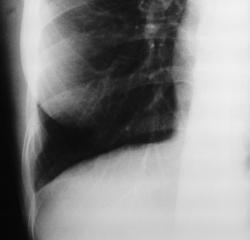

Такие находки я оцениваю весьма положительно, ибо такую теневую картину может давать и паракостальный осумкованный плеврит и эпителиома.

Я бы склонился к осумкованной жидкости, причем травматической природы. А эпителиома (мезотелиома) плевры, если не скрыта в вырабатываемой ею жидкостьюЮ как правило более кругленькая. А вот и ссылка http://www.radiomed.ru/cases/sochetannaya-patologiya-ochagovyi-v-dalneishem-infiltrativnyi-tuberkulez-levogo-legkogo-i-epit

Спасибо! Действильно, отграниченное скопление жидкости, доказано на УЗИ. Правда, факт травмы отрицает.

Паракостальная гематома: этот термин есть. Такие гематомы мы часто видин на КТ после травмы грудной полости с переломами рёбер. Гематомы это находятся кнаружи от париетальной плевры (а не между париетальными и висцеральными листками); как бы фокально "отслаивая" висцеральную плевру от предлежащих тканей и создавая полулунное "вдавление" в грудную плость. На КТ это хорошо видно, большого клин. значения (при малых размерах) не имеет.